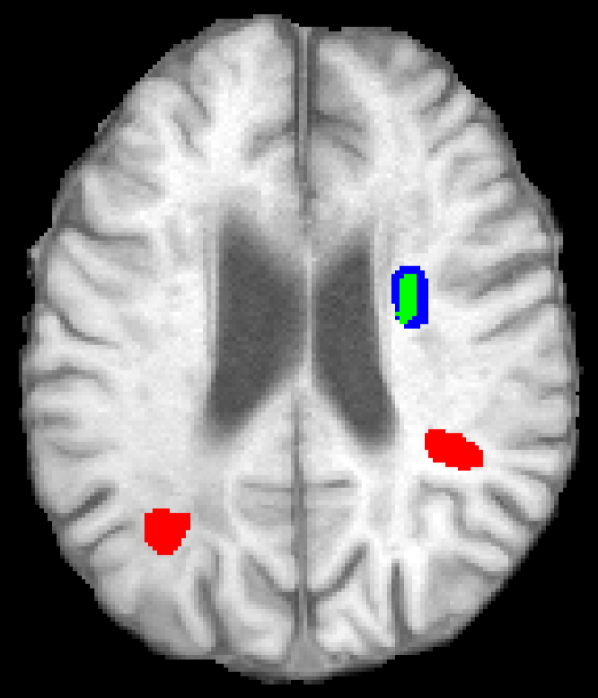

Representative examples of the qualitative results from the proposed method can be found in Figure 4. Cases 9 and 15 represent the overall results of the proposed methodology, correctly detecting the lesions in most cases with an outline that approximates the provided gold standard. Among the observed limitations are inaccurate borders and over/under segmentation of certain regions. For instance, in case 5 the lesion was undersegmented due to a heterogeneous appearance of the gold standard lesion while in case 13 two false positive lesions are detected due to the previous existence of chronic stroke lesions with a similar appearance.

Figure 4: Output segmentation masks of representative cases from the training images of ISLES 2015 SISS dataset. On all images, true positives are denoted in green, false positives in red and false negatives in blue.